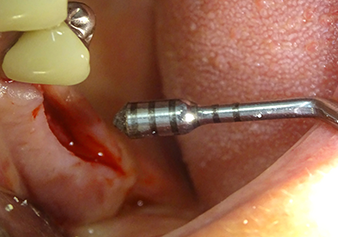

Затем, с помощью инструмента I2A (диаметр 2,0 мм), дно пазухи перфорировалось периодически и в минимально возможном диапазоне. Этот специфический пьезохирургический метод гарантирует, что мембрана Шнейдера не будет повреждена. При использовании Z25P, мембрана уже была слегка приподнята охлаждающей жидкостью, подаваемой через наконечник инструмента (рис. 3). Во избежание высокого давления в ложе имплантата, количество охлаждающей жидкости составляло не более 50%.

Рис.3: После маркировки положения имплантата и первоначального расширения ложа, мембрана Шнейдера деликатно отделяется с помощью инструмента Z25P (фаза 1).